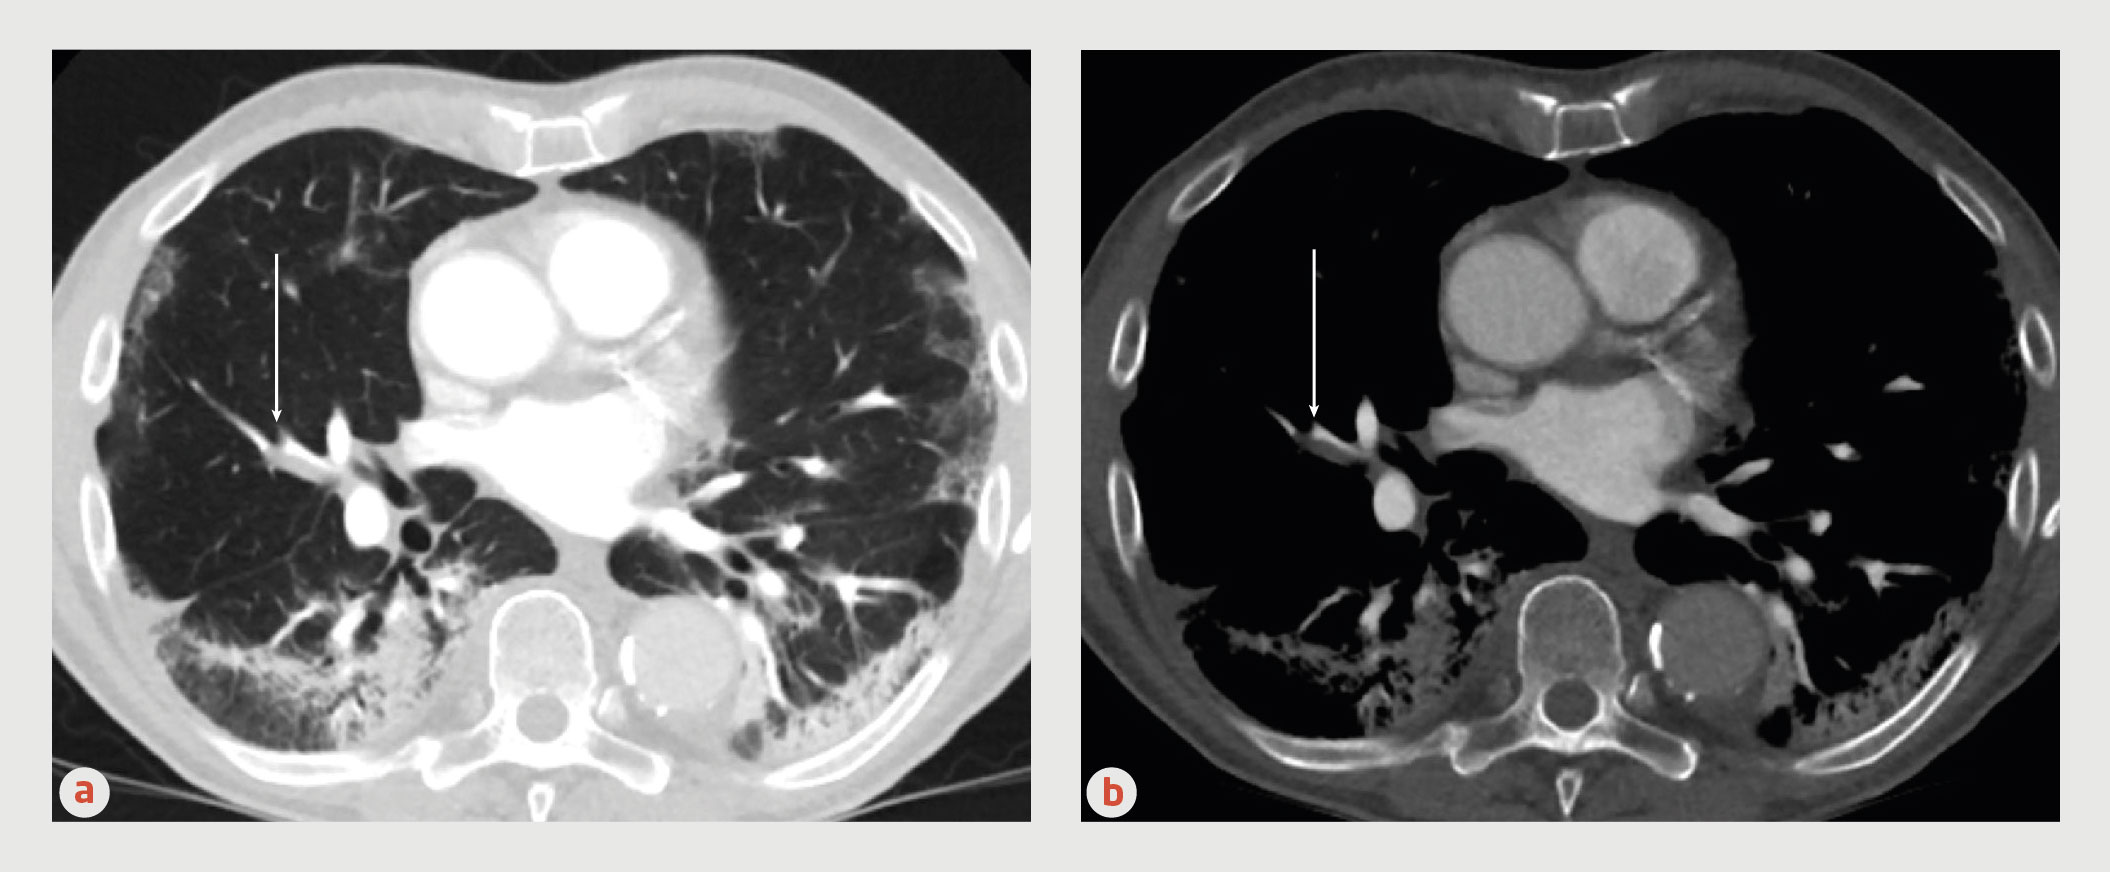

Figuur | Longembolie op CT-scan

CT-pulmonaire angiografie (CTPA) van een 76-jarige patiënt met COVID-19, (a) longsetting en (b) CTPA-setting. Bij deze patiënt nam de hypoxemie plotseling toe. Omdat er geen andere aannemelijke verklaring was, werd aan een longembolie gedacht. Er was 1 YEARS-item aanwezig (longembolie meest waarschijnlijke diagnose) en de D-dimeerwaarde was > 5000 ng/ml. Er werd een CTPA verricht, waarop een onderbreking van een longslagader werd gezien (witte pijl), bewijzend voor acute longembolie. Ook was een karakteristiek beeld van COVID-19 zichtbaar: multifocale, deels confluerende, relatief scherp begrensde matglasafwijkingen met superponerende gebieden van consolidatie, en fibrotische veranderingen met tractie aan fissuren in de ondervelden.